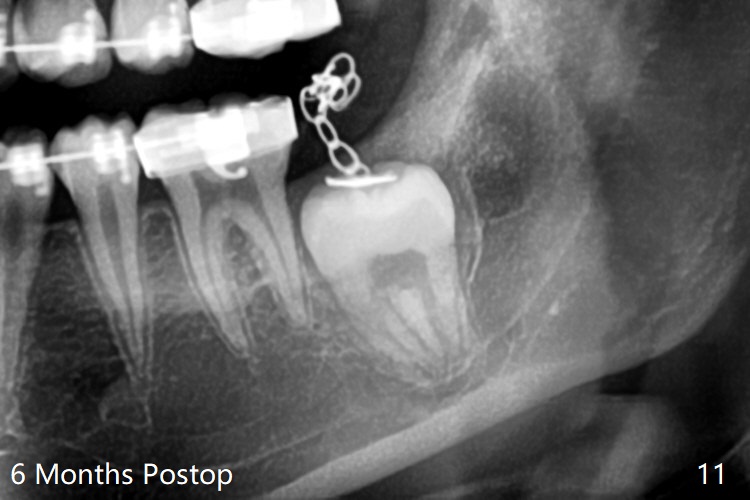

Treatment planning of surgical access to the impacted 7 (Fig.1) before CT analysis (to be canceled due to finance) include extraction of 8 (Fig.2) and removal of the bone coronal to 8 (Fig.3 red) so that there will be no bony block to 7 eruption (Fig.4). Place PRF or collagen plug in 8 socket to facilitate healing (Fig.3). Attach a retraction chain to the occlusal or buccal surface of 7 (Fig.6 pink) whenever it is convenient in term of hemorrhage and access (as mesial as possible). Remove 16 niti wires for brushing when the patient arrives. Cut 18 ss wire longer in the LL end (Fig.6 green to be bent to hook power chain (yellow)). Incision is shown as red in Fig.5. After 3 month delay, the thick buccal plate is removed from LL8 (1st) and 7 (2nd in sequence, as compared to Fig.2) to expose these unerupted teeth. In fact CT is not taken to decrease budget on the divorcing parents. A retraction chain is placed before extraction of LL8 with an intention to reduce hemorrhage (Fig.7). Although extraction requires several sectioning of the tooth, hemorrhage is mild to moderate. Instead of PRF and sticky bone (as compared to Fig.3), Osteogen plug is placed in the socket (Fig.8 OP). The bony septum between the 2 sockets is intentionally kept in place (*). 事实的确这样发生(图九:*)。埋伏牙不仅上移(^),而且远中移动(>),因为牵引方向(红虚线(橡皮筋),挂在上牙弓丝(图九:20ss:图十:18ss(之前))远端勾,积极牵引三个星期)。下次左上7放置舌侧纽扣,让病人更换橡皮筋。其实纽扣粘不住,上牙弓丝远中勾也不现实,只能使用橡皮筋挂在左上6,经常断。术后6个月,左下7继续上移(图十一)。这种低效率牵引仍然有效,牙齿继续上移,牙根长长(图十二:空箭头),但是受到左下6远中阻挡(*),所以下次在左上7咬合面装置舌侧纽扣和closed spring,改善牵拉方向(红箭头)。